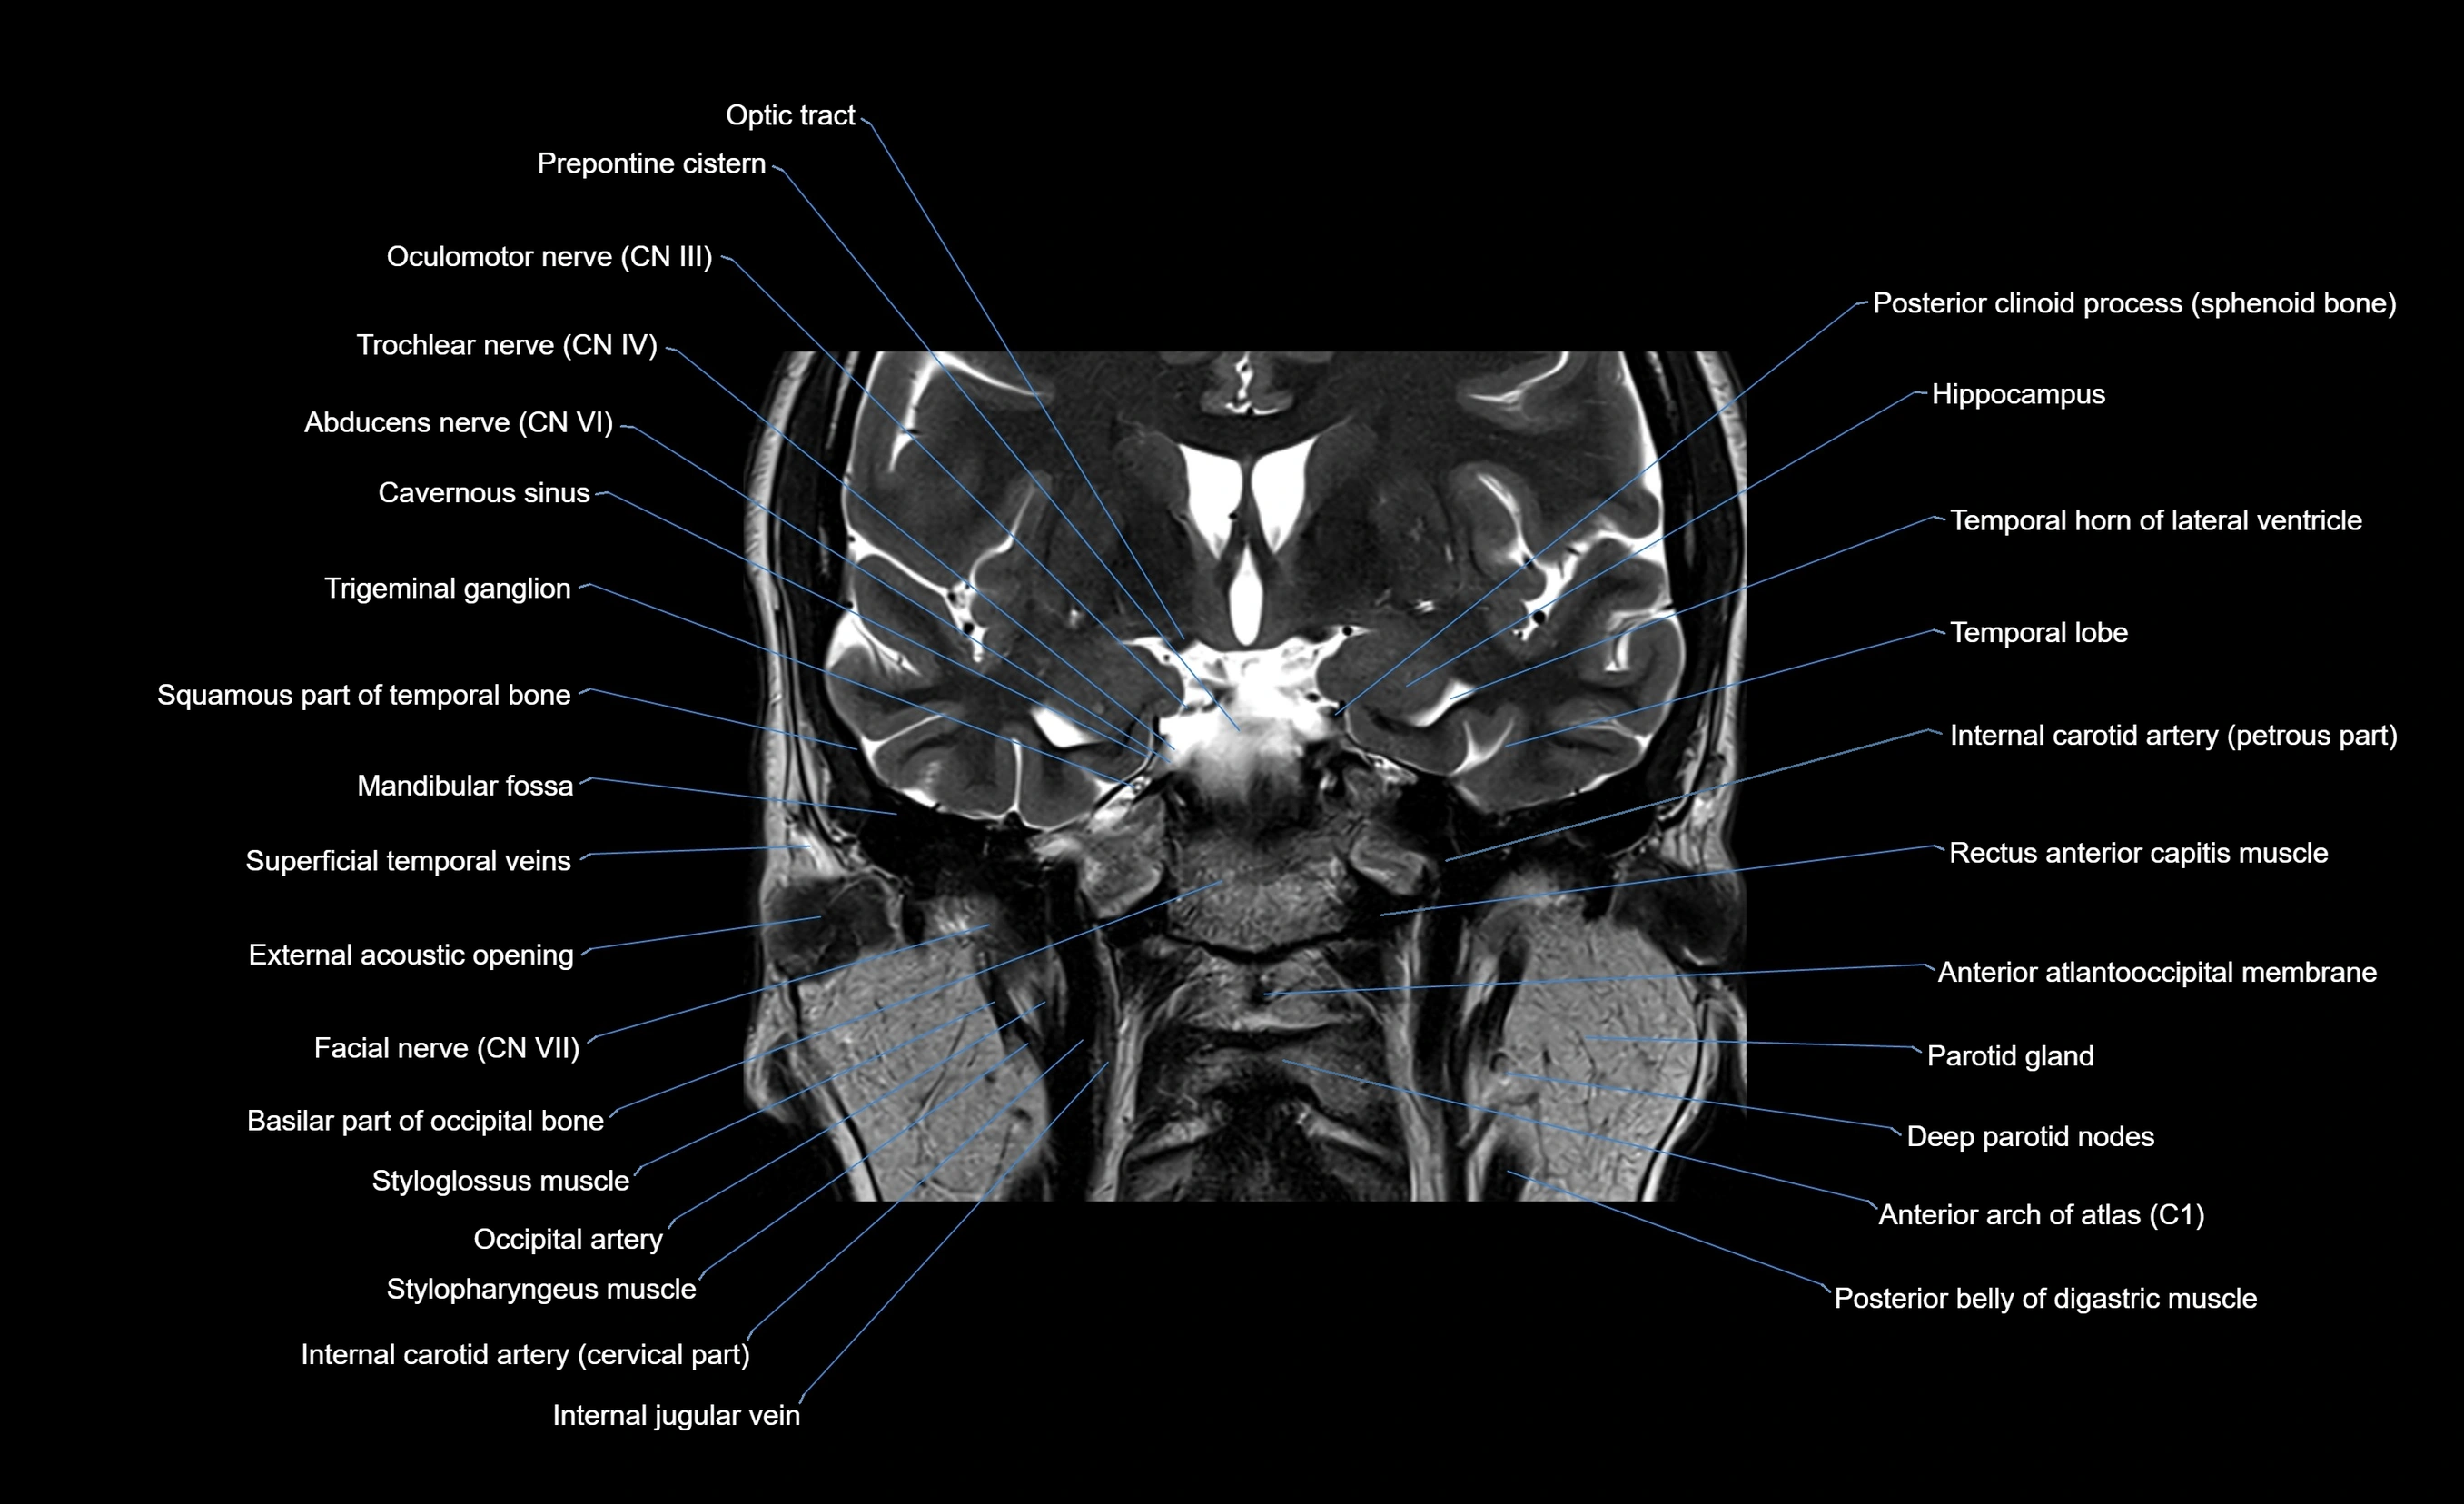

MRI images